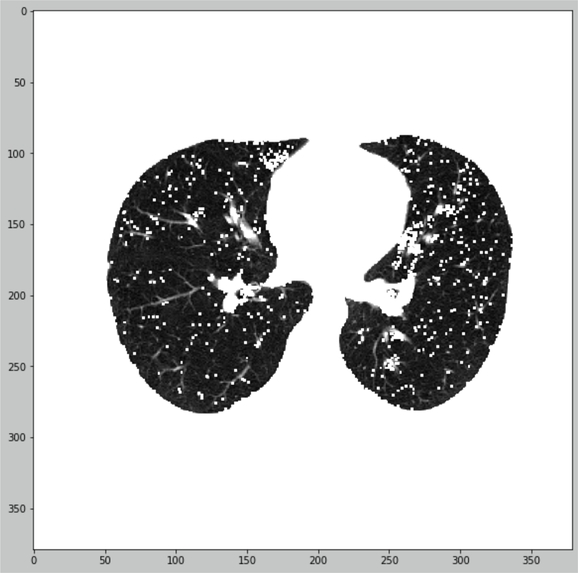

We offer the principle of lungs CT-images quantification with segmentation preprocessing

- Lungs masked and segmented

- Mask applied and lungs tissue HU-values calculated